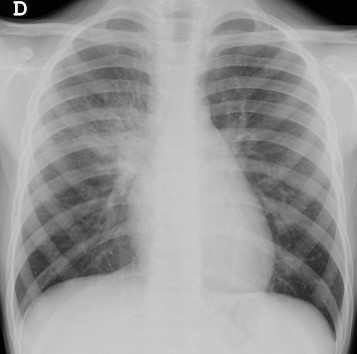

Patrón alveolar: es un patrón caracterizado por un aumento a densidad agua del parénquima pulmonar por ocupación de los alveolos, de aspecto algodonoso con márgenes poco definidos y que tiene distribución segmentaria o lobar. Puede presentar estructuras bronquiales llenas de aire en su interior (signo del broncograma aéreo). Es el patrón más frecuente de las neumonías bacterianas.

Patrón intersticial: sucede por afectación del intersticio, que origina imágenes de aumento de densidad de morfología lineal, reticulares o nodulares, de predominio perihiliar. Existen engrosamientos peribronquiales y suelen asociar atrapamiento aéreo. Es típico de las bronquiolitis.

Patrón atelectásico: aumentos de densidad triangulares con signos de pérdida de volumen (desplazamiento de cisuras, diafragma o mediastino). Pueden ser lobares, parcheadas, subsegmentarias o lineales.